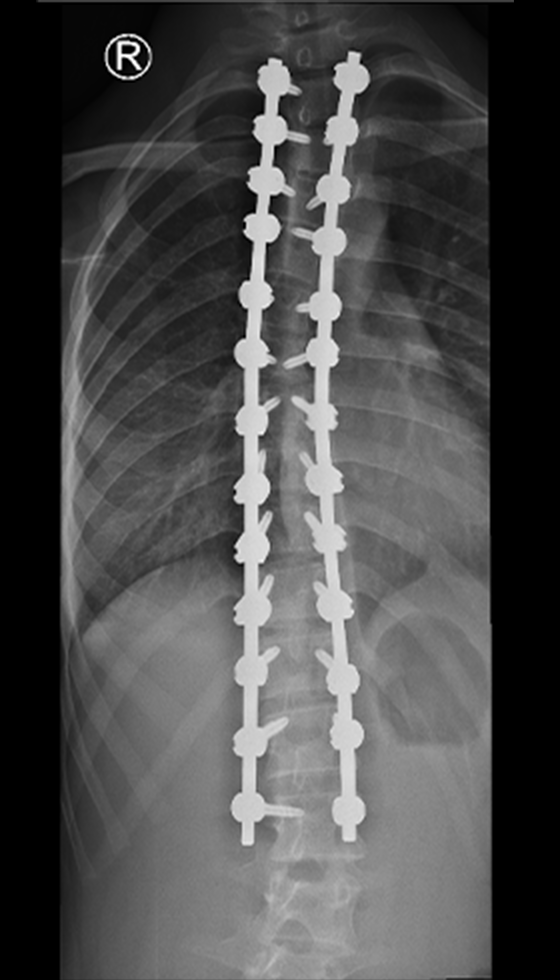

The procedure involves repositioning the spine and securing it with Screws and Rods. Bone graft is then placed so the treated vertebrae gradually heal together into one solid segment. This creates long-term stability, preventing further curve progression and improving overall alignment.

Gallery : Before - After

After

Before